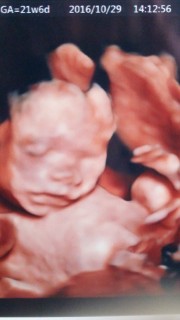

3d4dエコーを21週目から22週目ぐらいで撮られた方いますか? ? もし、差し支えなければ、ぜひかわいい赤ちゃん見せてください♡ 私は21週目なんですが、今週エコー外来行こうか迷っています。 3月9日 お気に入り 妊娠21週目 妊娠22週目 赤ちゃんJun 02, 17 · 週の健診でも24週でも女の子と言われ、まわりにも女の子と言っていました。ところがなんと28週のエコーで「あ、男の子みたいだね。男の子の象徴がハッキリ見えるね!今まで上手に隠してたのかな?」と言われました。Oct 12, 17 · でも4dエコーしてもらった時は 鼻がでかすぎて 、えっ?ってビックリしちゃいました。笑 エコー写真がどれくらい正確なのか産まれた息子と比較してみたいと思います! 21週3日の4dエコー これは初めて4dエコーをした時の写真です。

Aug 18, 16 · 逆子はエコーで簡単に調べることができますが、性別がわかりにくいことがあります。性別がわかりにくい理由や、逆子と間違える可能性のある「横位」の概要を含めて、専門医師の監修記事でわかりやすく解説します。Oct 08, 19 · 妊娠21週だと0人なのです。 21週と22週の間には、"命の線引き"とも言える、厳然たるラインがあるのです。 "生きられる見込みがない" 助けSep 24, · 妊娠21週目で性別がほぼ確定 しました。 そして、初めて4dエコーも見せていただきましたよ~! 妊娠21週目の4dエコー写真 ちょっとわかりにくいかもしれませんがこちらを見ている

妊娠週 21w3d 4Dエコー外来に行ってきました。 画像の中の赤ちゃんの動きと同時に胎動を感じた時すっごく感動しました。 写真はニコッと笑ってくれた瞬間でした。 おなまえ さと ねんれい 27 妊娠週 21w3d 今回は真っ正面でエコーがとれました (*^^) 笑っDec 19, 19 · 妊娠21週 3dエコー写真「すごい、つり目」が気になる 妊娠22週 スペインでのクリスマス 妊婦が食べられない料理が多い(涙) 妊娠23週 帝王切開か自然分娩(vbac)かで迷う 人気記事 妊娠24週 胎動が激しい!産まれてくる子は癇が強い!Sep 05, 19 · 妊娠22週目の女の子のエコー写真 右上がおしり、左下に向かって2本の足が生えています。 こちらはコーヒー豆や葉っぱのような割れ目(シンボル)のようなものが見えるのが分かりやすい写真です。 妊娠25週目の女の子のエコー写真